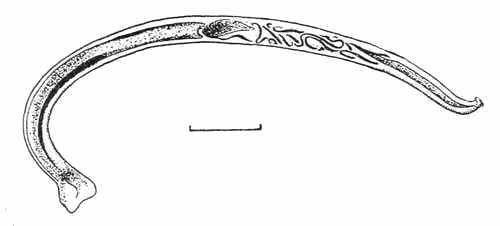

| XXVI. | Hookworm Disease and Amoebic Dysentery | 120 |